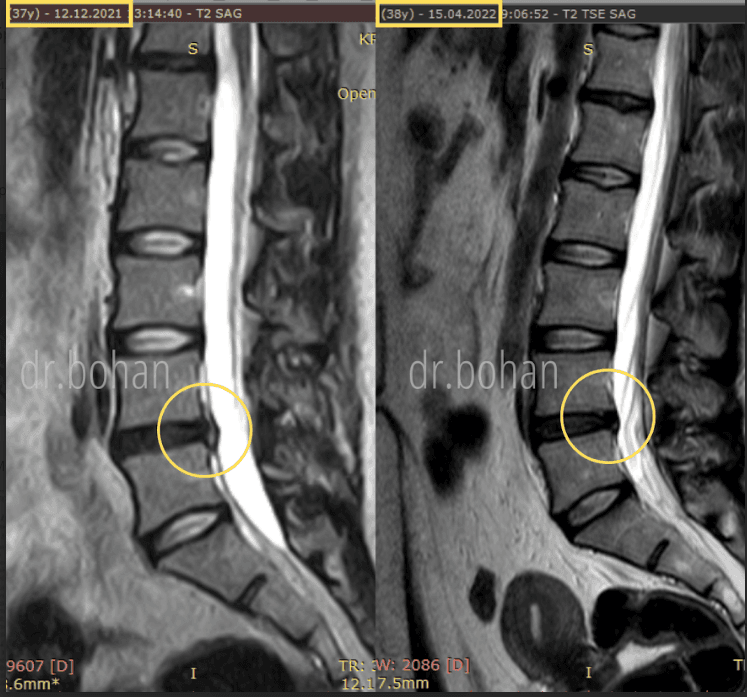

Метод лікування грижі шляхом стимуляції резорбції в Україні був впроваджений у 2020-2021 роках.  Алгоритм оцінки грижі на предмет резорбції, що використовується у клініках – є авторським, розроблений лікарем Боханом А.Ю.